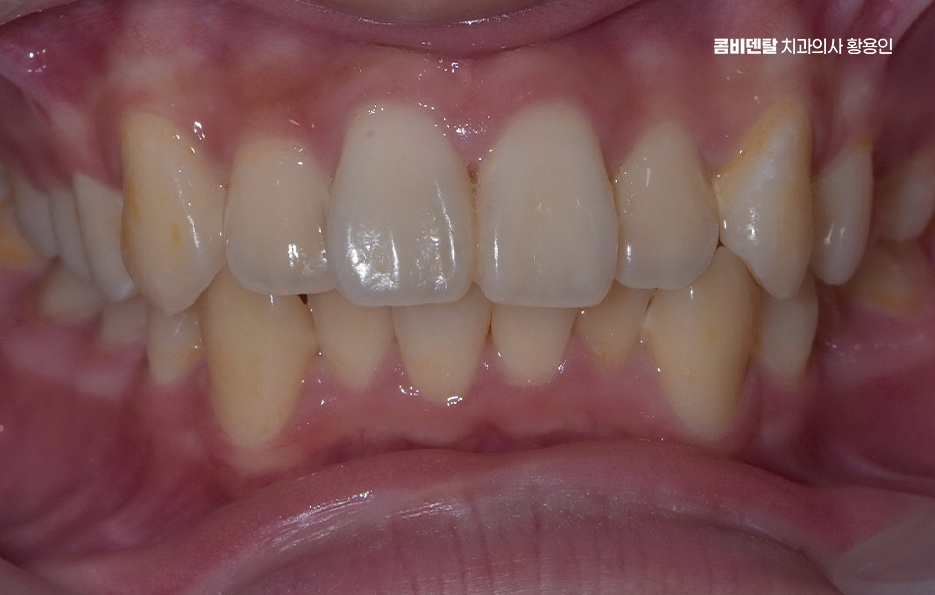

웃을 때 앞니가 살짝 겹쳐 보이고, 어금니 쪽이 조금씩 안 맞는다는 느낌이 들었지만, 크게 문제가 없다고 생각했어요. 밥을 씹을 수 있고, 말할 때 발음이 불편하지 않고, 치아 사이에 뭐가 많이 끼는 편도 아니라서 그냥 이런 게 사람마다 다른 치아 구조겠거니 하며 지내왔어요 그런데 어느 날부터 씹을 때 한쪽 어금니가 더 무리되는 느낌이 들고, 자고 일어났을 때 턱관절이 뻐근한 날이 잦지기도 했어요

특히 교합이 틀어진 상태에서는 특정 치아에만 씹는 힘이 과도하게 실리게 되는데 이로 인해 일부 치아는 빠르게 마모되거나 깨지게 되고, 반대로 거의 사용되지 않는 치아는 치주 조직이 약해져서 잇몸 퇴축이나 치주염이 생길 확률도 높아지는 거예요. 그리고 치열이 고르지 않은 상태에서는 양치질을 꼼꼼히 해도 치간이나 치아 뒷면에 음식물과 세균이 남기 쉬워서 충치 발생률도 높아지는 건 당연한 것이며 결국 부정교합은 기능적인 저작 문제, 치아의 수명 단축, 잇몸 질환이라는 복합적인 문제로 이어지게 될 수 있어요

부정교합 교정 안하면 심미적인 측면에서도 부정교합을 방치하는 건 얼굴 전체의 이미지에 영향을 줄 수 있어요. 예를 들어 돌출입, 무턱, 비대칭 턱, 잇몸 웃음 같은 문제들은 단순히 치아 배열이 아니라 위아래 턱의 관계와 근육 균형에서 기인하는 경우가 많고 교정치료를 통해 치아를 올바른 위치로 이동시키면 얼굴형 자체가 정돈되고 입술선도 자연스럽게 정리되는 효과가 있어요.